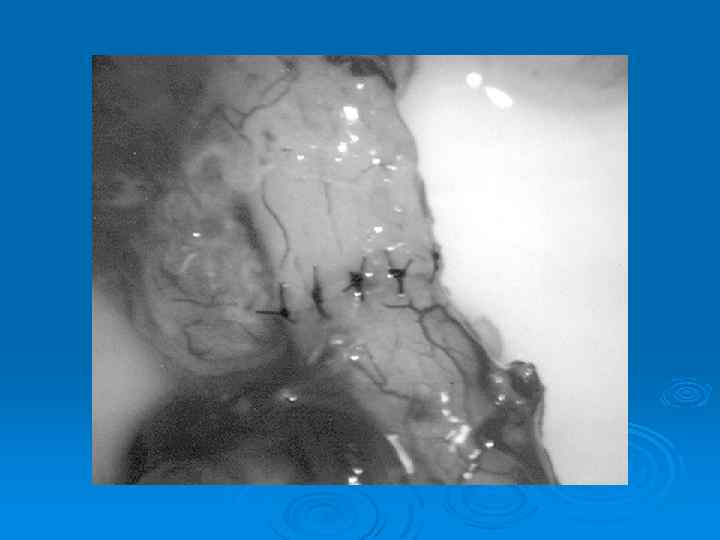

Вазоэпидидимостомия